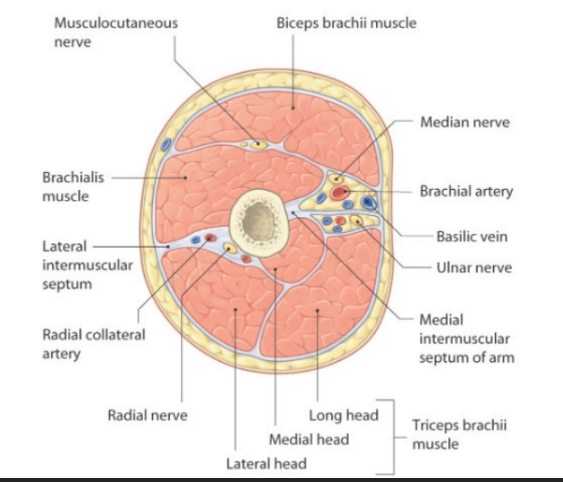

Compartments of arm

Medial and lateral intermuscular septae arises from deep fascia and divides arm into flexor and extensor compartment

Contents of flexor compartment

Muscles- biceps brachii, coracobrachialis and brachialis

Nerve- musculocutaneous

Artery- brachial

Contents of posterior compartment

Muscles- triceps

Nerve- radial